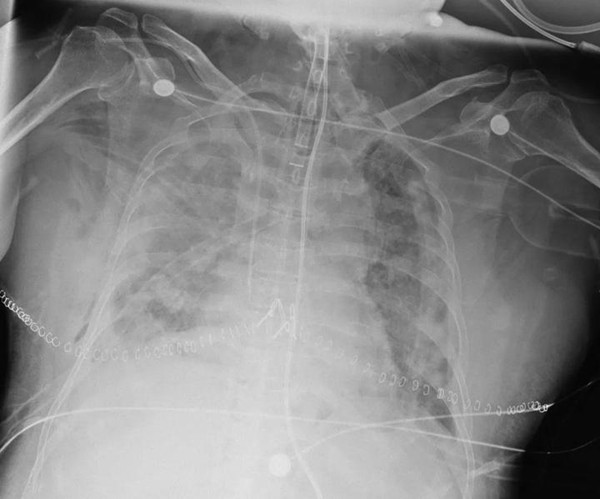

術后

雙肺順利移植完成。

在場的醫護人員來不及慶祝,馬上又投入到新一輪的戰斗中。由于患者術后還面臨著肥胖造成的呼吸功能影響等問題,必須時刻密切監護。重癥監護專家們早已在交接點等候,將患者平安護送至監護室,生命的接力,繼續上演。

肺移植科主任韓威力術后回憶,整個手術過程險象環生,特別是患者肺靜脈左房袖吻合處的處理尤其困難,稍有不慎,要么左房無法吻合,或者阻斷鉗滑脫,直接導致患者死亡。“好在團隊經驗豐富合作默契,問題一一化解。”